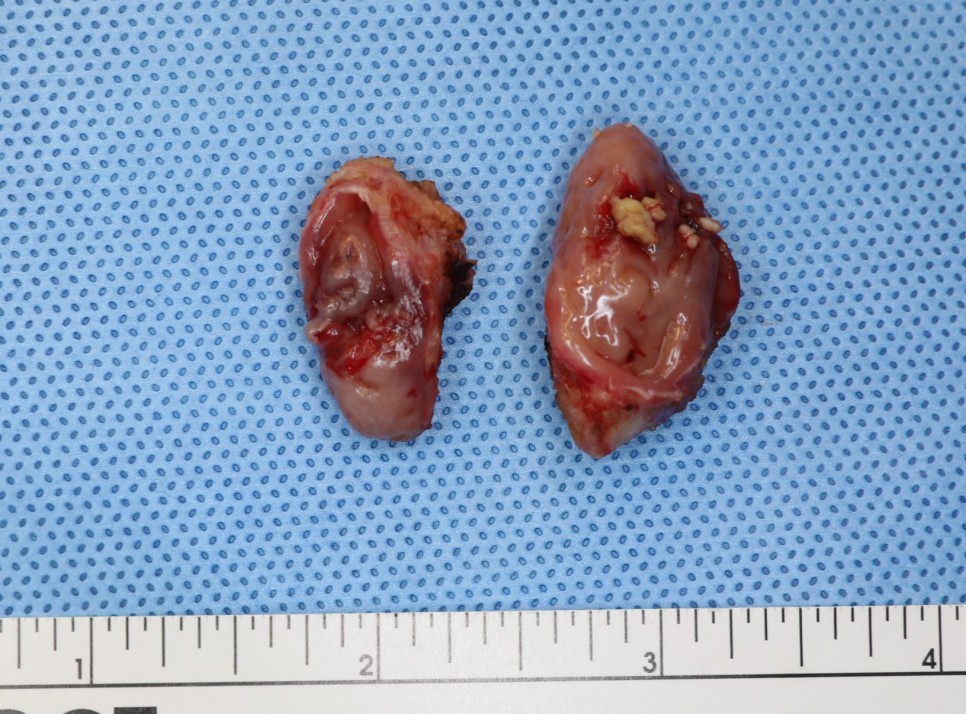

편도완전절제술 TOTALTONSILLECTOMY

편도 결석이 있는 분은 대부분 만성 편도염을 앓는 경우가 많기 때문에 수술 중 출혈이 많지요. 다행히 오늘 환자는 출혈이 많지 않았어요. 대부분 코브레터 편도 절제술은 출혈이 많지 않으면 양측 절제에 15분에서 30분 정도 걸립니다.

이 환자의 경우 심부 60% 정도에 이르기까지 편도 내에 다량의 결석이 존재하고 있었습니다. 수술하면서 편도를 잡고 누를 때 상당한 양의 편도 결석이 밖으로 튀어나왔습니다.

완전 절제가 잘 되었기 때문에 앞으로 재발은 없을 것입니다. 수술 받느라 고생 많았어요!! 그리고 일주일 남은 수술후 아픔도 견뎌내세요. (´;ω; ))